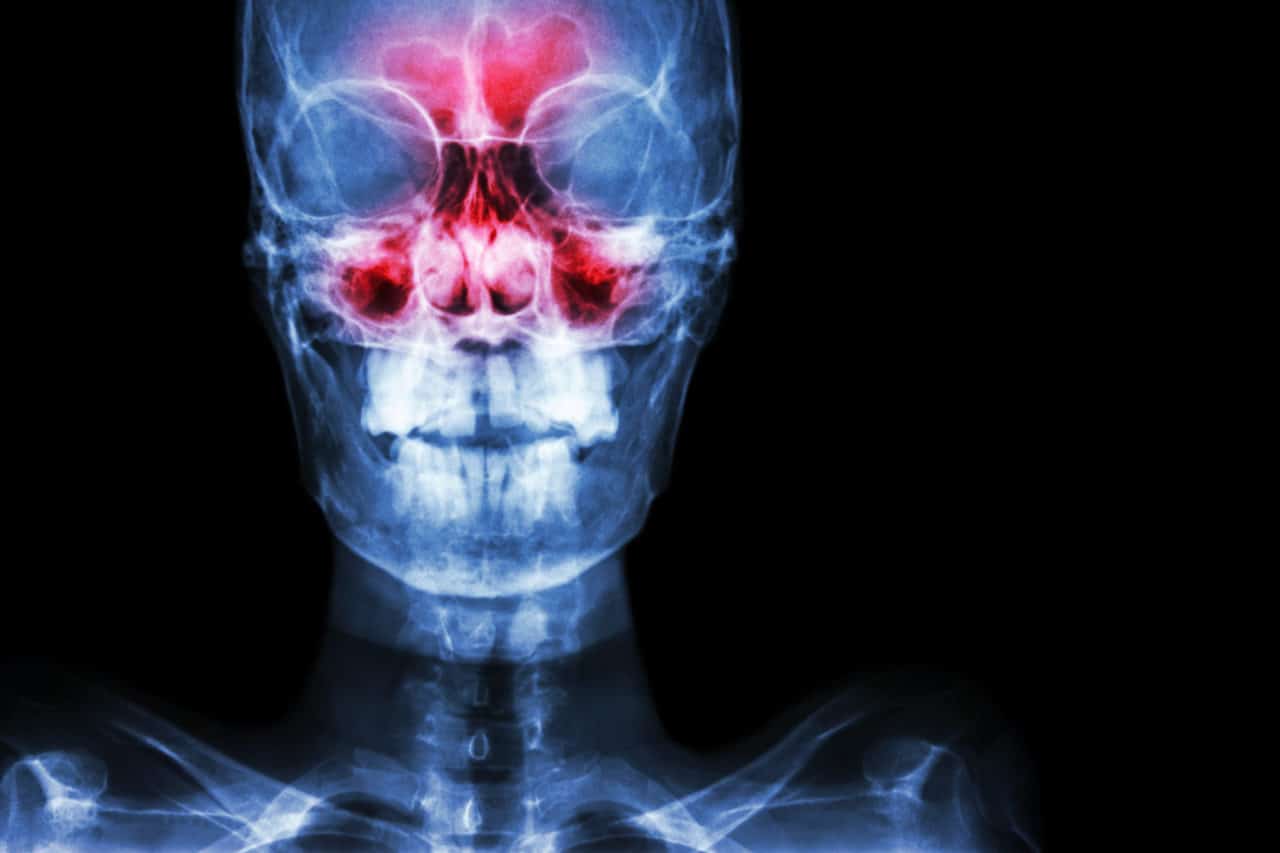

Sinusitis is inflammation and swelling of the tissues that line the sinuses. This interferes with normal mucus drainage, leading to breathing difficulties, pain and pressure. When the condition persists for 12 weeks or longer, it is considered chronic.

In addition to a physical examination and a review of your medical history, your doctor will inspect your nasal passages for polyps and other abnormalities and check for inflammation and a buildup of fluid. Additional tests utilizing nasal endoscopy, CT scans, MRIs and allergy tests can be used to help confirm the diagnosis.